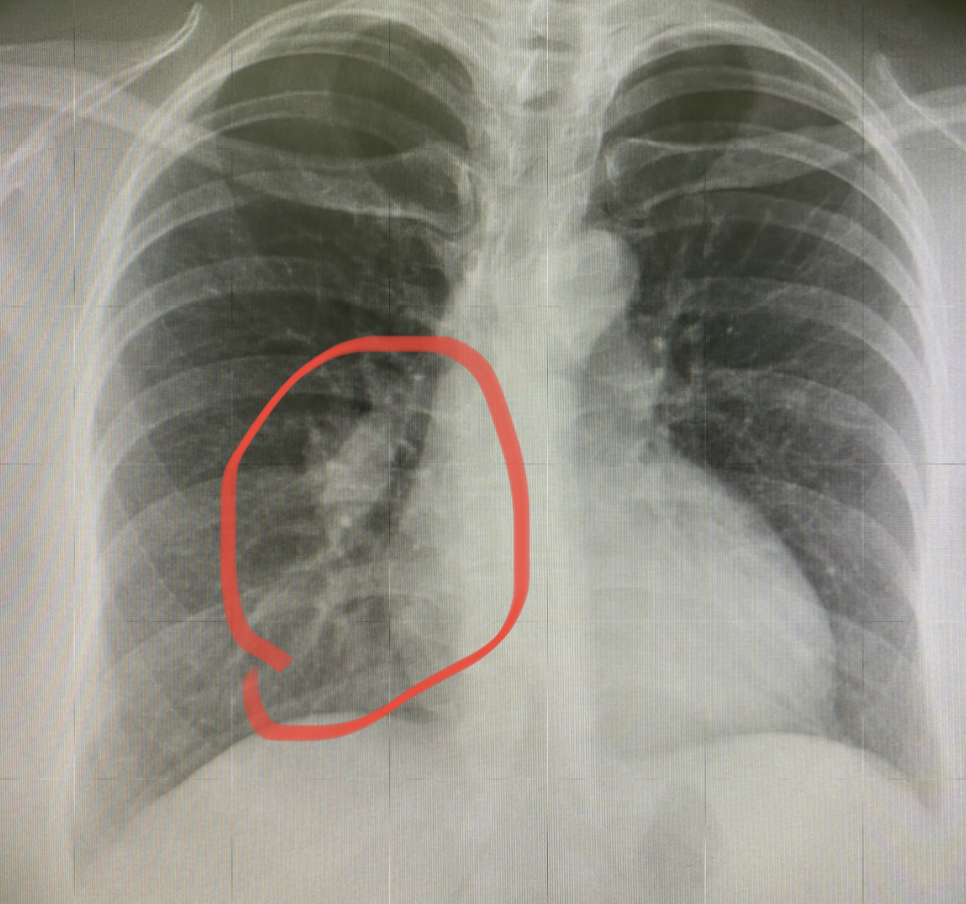

做了胸片,发现右肺有肺炎样的改变